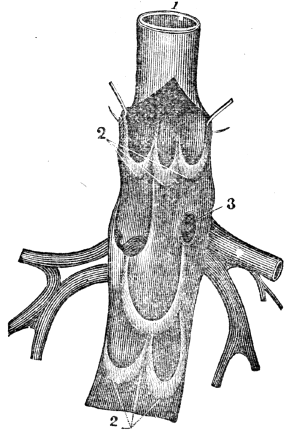

| 17. | Anatomy of the Circulatory Organs, | 154 |

| 18. | Physiology of the Circulatory Organs, | 164 |

| 19. | Hygiene of the Circulatory Organs, | 172 |